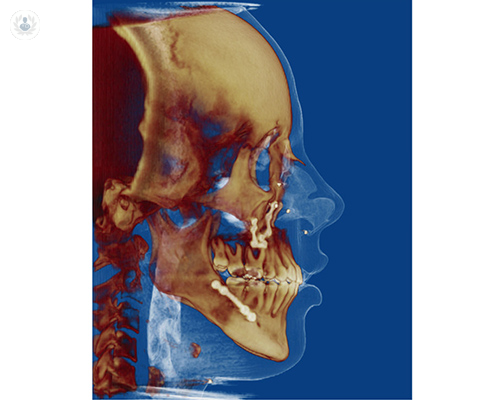

Guías y miniplacas personalizadas: un protocolo guiado para cirugía ortognática

El Dr. Joan Brunsó explica en qué medida ha ayudado la introducción de la tecnología en el tratamiento de problemas orales y maxilofaciales, como la cirugía ortognática. Conoce en qué consisten las guías y las miniplacas en cirugía ortognática, los métodos y los materiales utilizados...